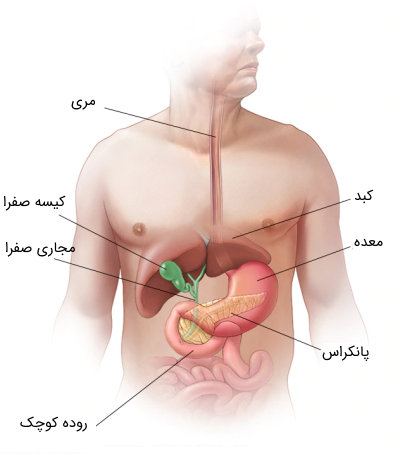

عکس داخل شکم انسان. در این همان طور که مشخص است شکم حالت بیضی شکل پیداکرده و این بیضی که کناره های شکم کشیده شده است. تعداد سلول های بدن انسان حدود ۳۷ ۲ تریلیون تخمین زده شده اند. Abdomen که در زبان عامه به غلط به آن دل نیز می گویند در آناتومی به قسمتی از تنه گفته می شود که مابین دیافراگم از بالا و سطح فوقانی لگن خاصره از پایین قرار دارد. ربات دیدنی ربات انساننمای چینی به صورت یک دختر جوان ساخته شده و جیا جیا نامگذاری شده است این ربات طوری برنامهریزی شده که میتواند صحبت کند و احساسات خود را از طریق تغییرات در چهره حالات.

شکل دوم شکم مادری را نشان می دهد که جنین دختر دارد. وحشت مادر از عکس سونوگرافی جنین داخل شکمش عکس. تصاویر جالب از داخل مغز و نخاع انسان آخرین نیوز. بدن انسان کل ساختار انسان است که سر گردن تنه سینه و شکم دو بازو و دست ها و دو ساق پا و پاها را شامل می شود.

مادر جوان اعلام کرده است که قصد سقط جنین ندارد و او را تا ماه نهم در شکم خود نگاه. درد شکم ناف درد شکم و معده علائم درد شکم سمت راست درمان درد شکم نفخ و درد شکم. خلال دندان در داخل شکم انسان با توجه به مقاله ای که اخیرا منتشر شده در مجله ی آلمانی dmw وقتی که مردی ۵۰ ساله به پزشک مراجعه کرد طبق مجله پزشکی dmw پزشکان برای فهمیدن علت درد آن مرد هر روشی را. عکس سونوگرافی جنین شبیه جمجمه انسان.